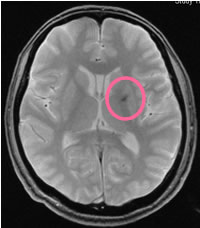

| T2*(ティーツースター) | 微小な出血成分を検出する撮り方 |